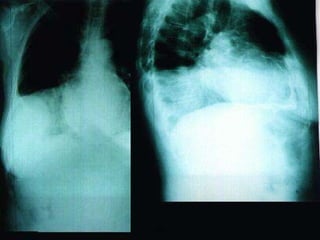

CARDIAC TAMPONADE pericardial effusion occurs when the space bet. the parietal & visceral layers of the pericardium fill with fluid.  Etiology: stab wound tumor surgery 2009

Cardiac tamponade   2009

CARDIAC TAMPONADE pericardialeffusion occurs when the space bet. the parietal & visceral layers of the pericardium fill with fluid. Etiology: stab wound tumor surgery 2009